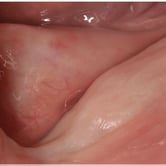

Atrofia ósea alveolar

La atrofia ósea alveolar es la pérdida de hueso en la mandíbula o el maxilar debido a la ausencia prolongada de dientes.

Los pacientes pueden notar que sus encías están hundidas y que las dentaduras no encajan bien.

El tratamiento puede incluir injertos óseos para preparar el sitio para la colocación de implantes.